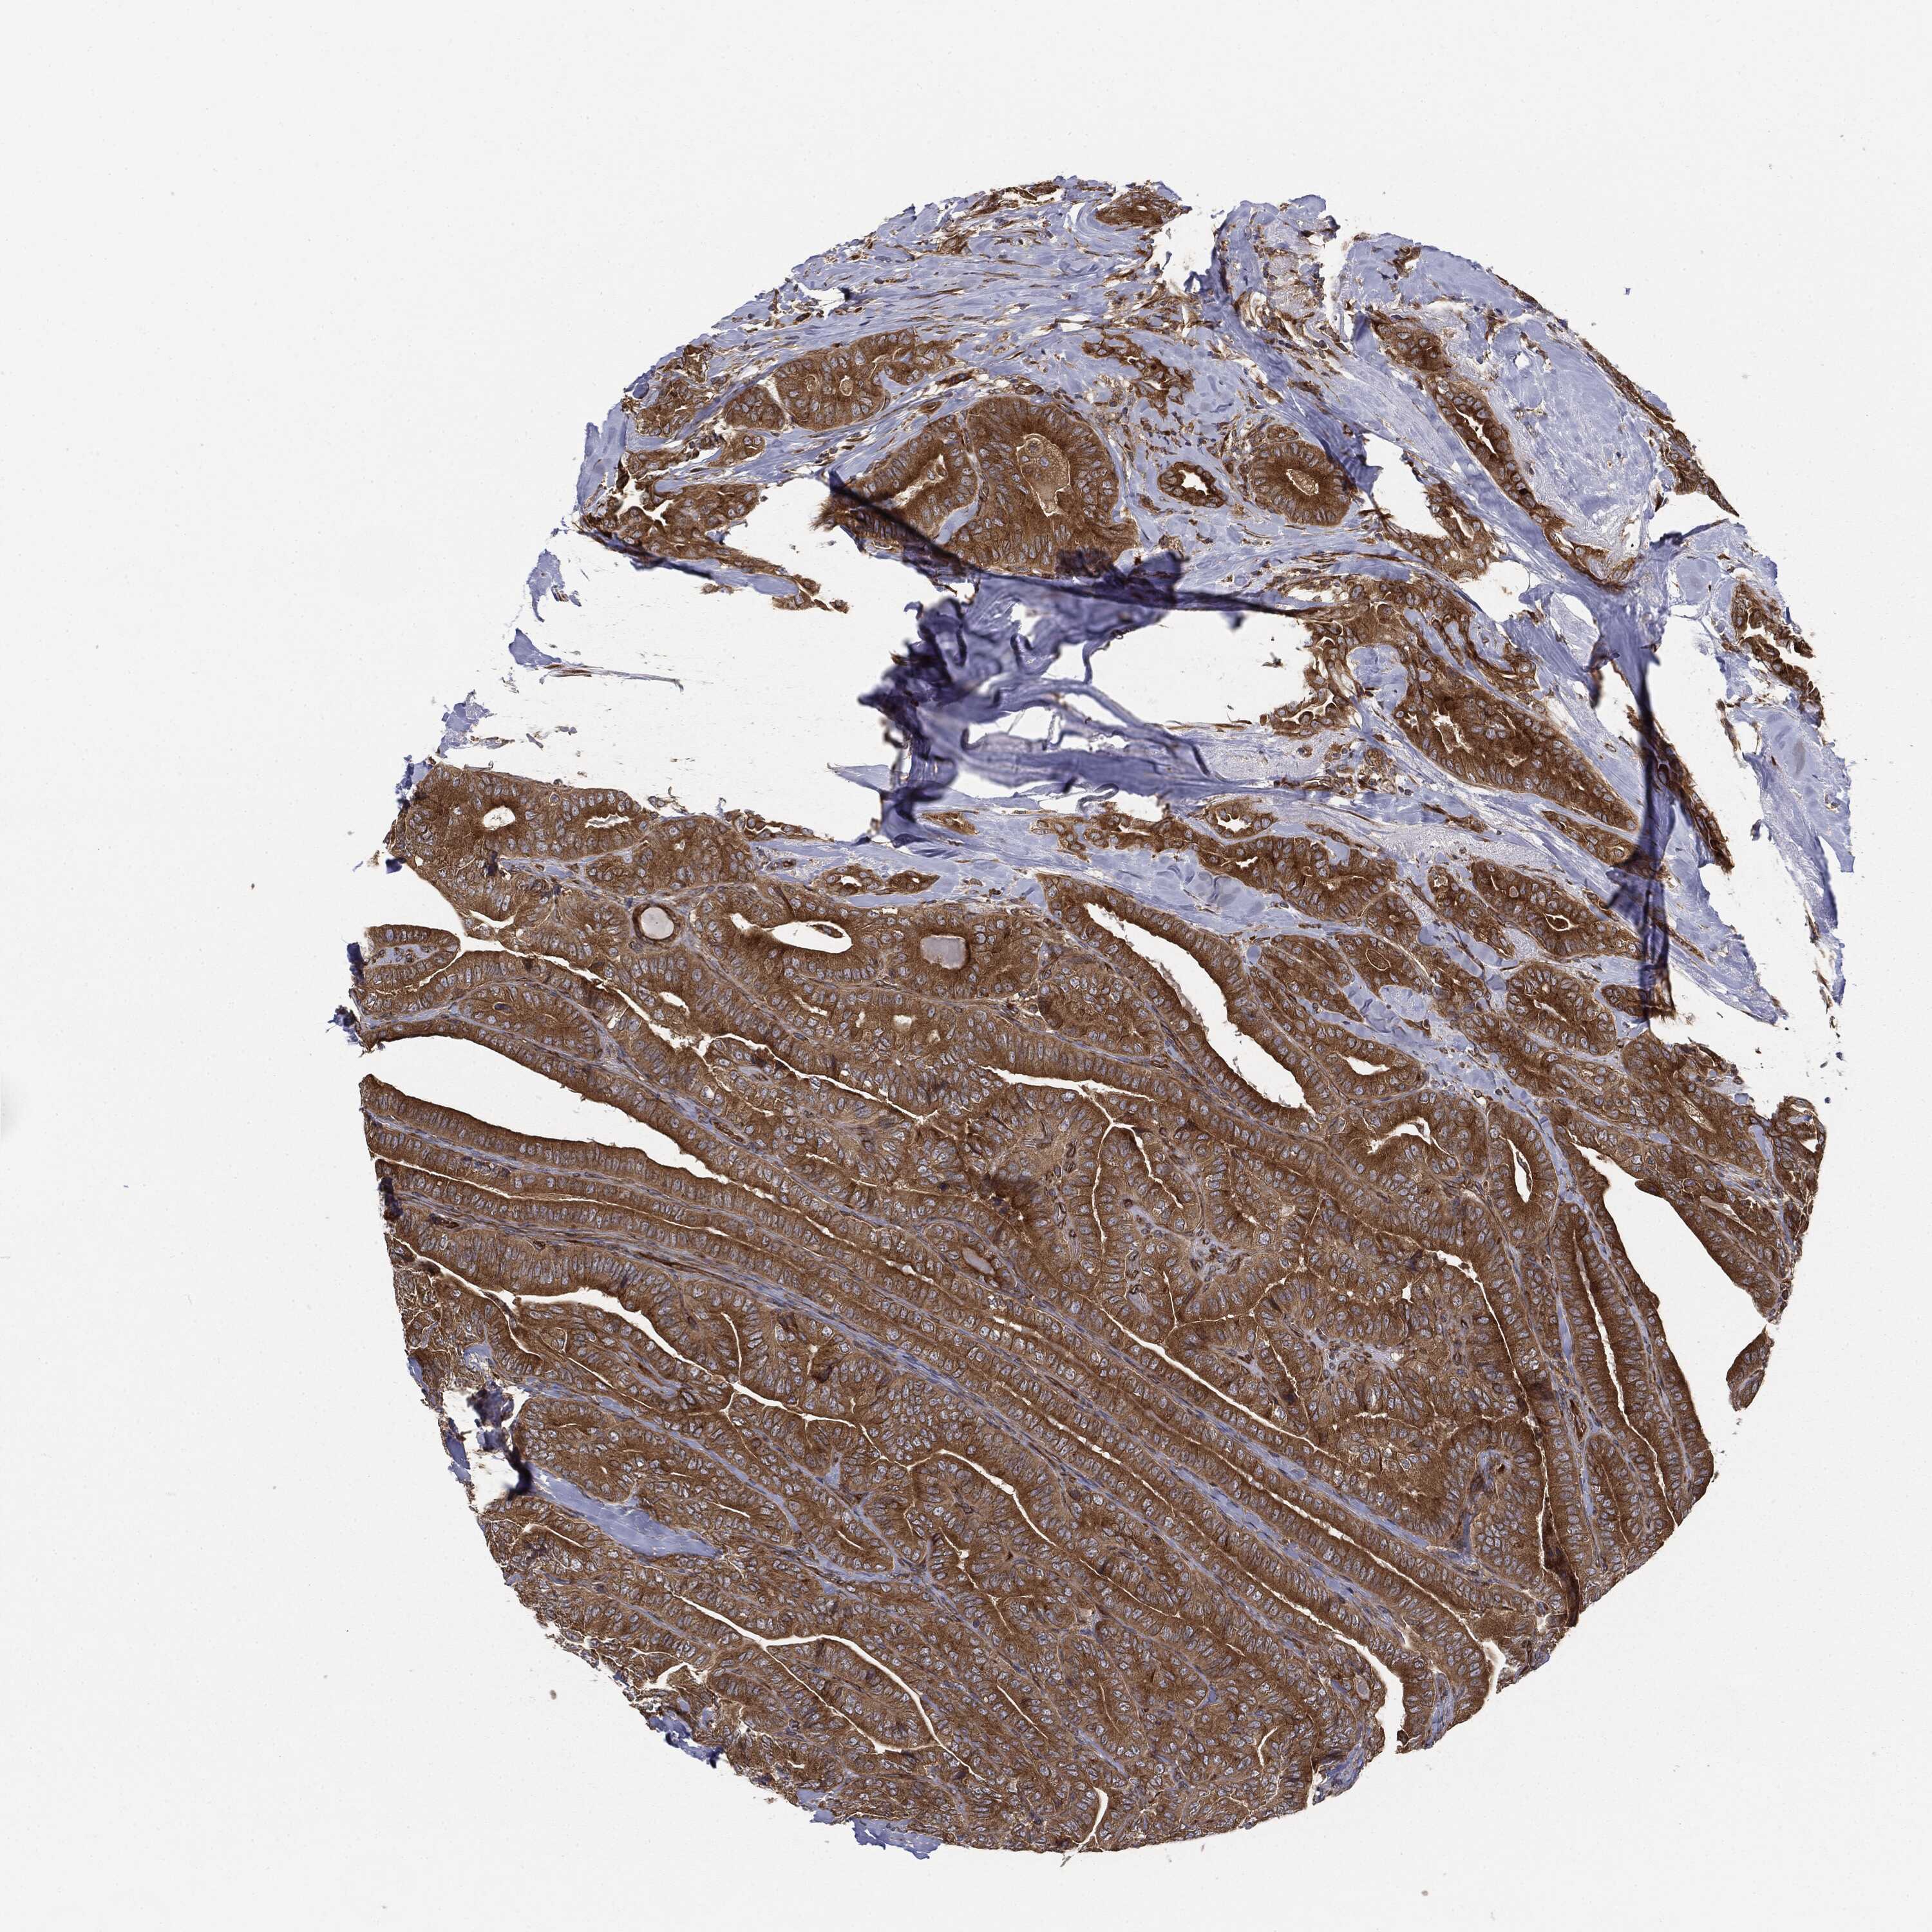

THYROID CANCER - Protein expressioni

A mouse-over function shows sample information and annotation data. Click on an image to view it in a full screen mode. Samples can be filtered based on level of antibody staining by selecting one or several of the following categories: high, medium, low and not detected. The assay and annotation is described here.

Note that samples used for immunohistochemistry by the Human Protein Atlas do not correspond to samples in the TCGA dataset.

Antibody stainingi

Antibody staining in the annotated cell types in the current human tissue is reported as not detected, low, medium, or high, based on conventional immunohistochemistry profiling in selected tissues. This score is based on the combination of the staining intensity and fraction of stained cells.

Each image is clickable and will lead to virtual microscopy that enables deeper exploration of all samples and also displays staining intensity scores, fraction scores and subcellular localization as well as patient and tissue information for each sample.

Antibody HPA019795

Antibody HPA063893

Antibody CAB003845

Staining

High

Medium

Low

Not detected

Intensity

Strong

Moderate

Weak

Negative

Quantity

>75%

75%-25%

<25%

None

Location

Nuclear

Cytoplasmic/membranous

Cytoplasmic/membranous,nuclear

Papillary adenocarcinoma, NOS

Follicular adenoma carcinoma, NOS

Carcinoma, NOS